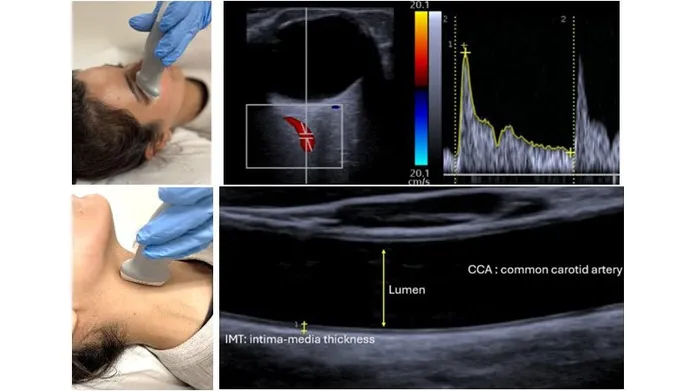

This is becoming more critically relevant in maternity especially as the obese and diabetic population is increasing in the younger age groups during their reproductive period. We need methods to improve our predictions of pregnancies at risk of hypertensive pregnancy to allow stratification of women at most risk, for future follow up. Endothelial dysfunction is a major hallmark of gestational hypertension and understanding the extent of microvascular dysfunction during and after pregnancy will help identify new therapy. Ultrasound imaging of the vasculature in different vascular beds will help us understand disease. In combination retinal imaging and subsequent AI analysis will identify potential biomarkers of endothelial dysfunction.

The overall objective of this study is to use radiography imaging technology to compare endothelial function in women during and after pregnancy to compare women with gestational hypertension and non-hypertensive gestational matched controls to understand cardiovascular disease progression.